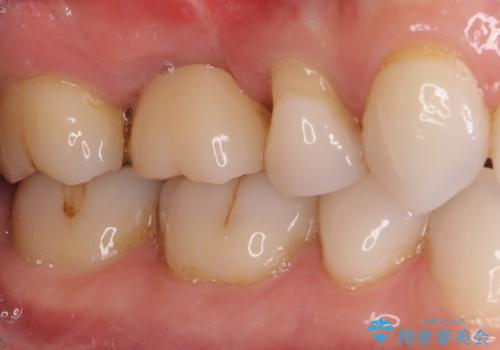

機能性と清掃性、更には審美性も考慮し、土台となるアバットメントにはジルコニアカスタムアバットメントを採用しました。

ジルコニアカスタムアバットメントは、歯肉ラインに金属が見えにくいというだけでなく、クラウンを装着する土台の形が天然歯と近い形態となるため、清掃性が高く歯肉が腫れにくいというメリットがあります。